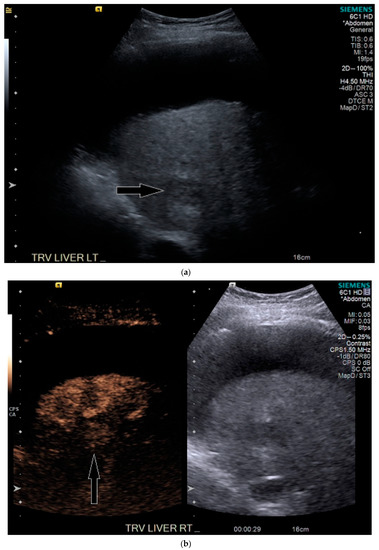

On grayscale imaging, a 2.9 cm hypoechoic lesion at the dome of the right lobe on a background of heterogeneous liver parenchyma was identified (Figure 5). Due to his acute on chronic renal failure, CEUS was then performed, which showed subtle enhancement of the lesion, above background enhancement of the adjacent liver at the same depth. At or greater than 10 cm depth is most often the limit of penetration in standard CEUS software packages [13], but can be extended in the presence of ascites, as in our case. Subtle washout was identified on delayed imaging, and the lesion was deemed LI-RADS 5 (Figure 5).

Figure 5.

Patient 3 ultrasound images, ascites is present with lesion denoted by white arrow: (a) grayscale images showing the hypoechoic lesion. Post contrast administration ultrasound in arterial phase shows subtle enhancement compared with liver parenchyma at the same level (b) and delayed phase mild washout (c) of the lesion, LI-RADS 5.